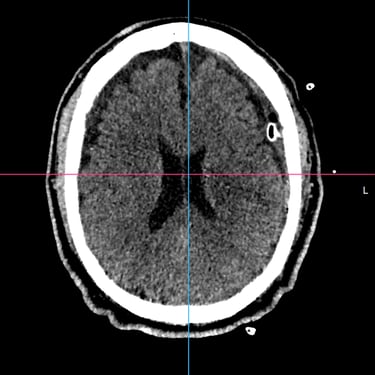

El hematoma subdural subagudo se caracteriza por la acumulación progresiva de sangre entre la duramadre y la superficie cerebral, generalmente posterior a un traumatismo craneal. Esta condición puede generar síntomas como dolor de cabeza persistente, confusión, debilidad en extremidades o alteración del estado de conciencia. El tratamiento quirúrgico consiste en la evacuación del hematoma mediante burr hole ampliado, técnica que permite realizar un orificio en el cráneo para drenar el contenido hemático y descomprimir el cerebro. Este procedimiento ayuda a disminuir la presión intracraneal, mejorar los síntomas neurológicos y prevenir complicaciones asociadas a la compresión cerebral.